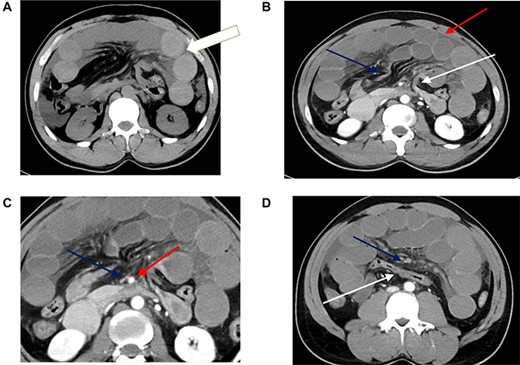

CT scan findings of transmesocolic hernia. (A) CT scan demonstrates hyperdense appearance of small bowel loops (arrow) suggestive of intramural hemorrhage. (B) Contrast enhanced CT scan demonstrates internal hernia with dilated bowel loops (red arrow), afferent loop at dudenojejunal junction (white arrow) and efferent loop (blue arrow). There is associated mesenteric congestion and free fluid. (C) Marked attenuation of the superior mesenteric vein (blue arrow) compared to the adjacent superior mesenteric artery (red arrow). Note also the congestion and fan-like. (D) The transverse colon (white arrow) is seen posteriorly with the congested small bowel mesentry (blue arrow) and dilated small bowel loops seen anterior to it. Note also the poor enhancement of the mesenteric veins.

Laboratory examination showed leukocytosis of 14 000/mm3 with normal lactate (0.8 mmol/l). An erect abdominal X-ray, including the diaphragm, did not show evidence of free peritoneal fluid. Abdominal CT (Fig. 1) showed dilatation of small bowel loops with a focal area of narrowing at the duodenal jejunal flexure and ileum, with the apparent collapse of small bowel and colon distal to the ileal narrowing. Furthermore, the posterior displacement of the colon was revealed. CT also revealed an abrupt narrowing of the superior mesenteric vein with poor opacification of the distal branches.